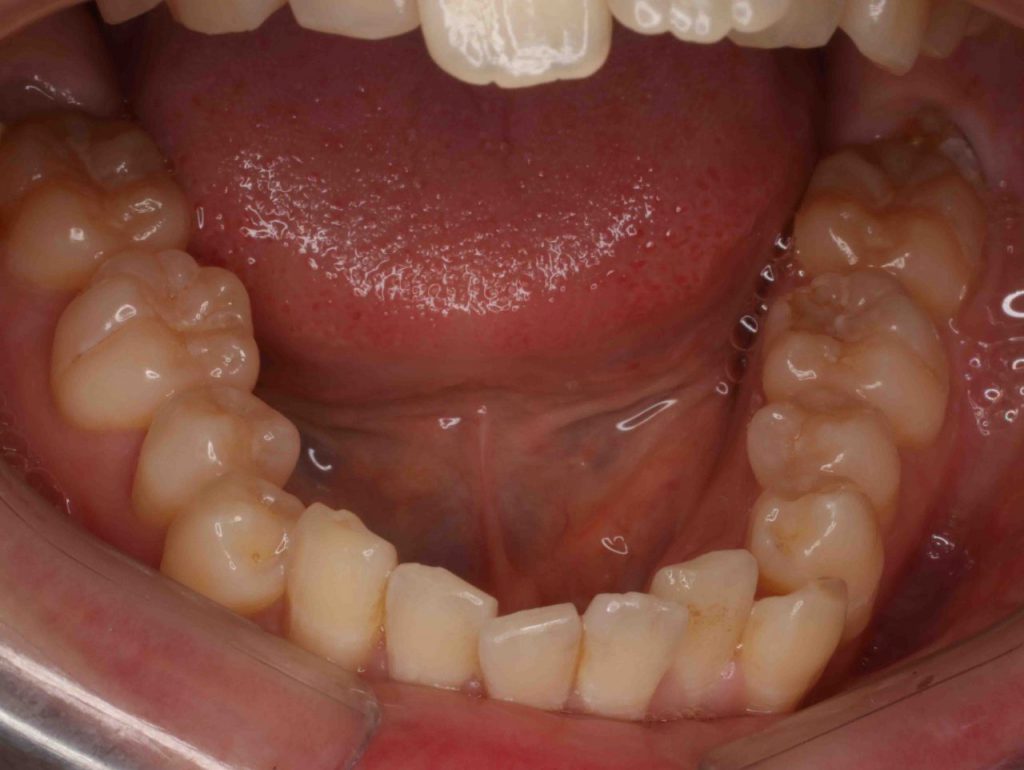

Before

Before

上の前歯が飛び出ている、出っ歯が気になる下の歯がデコボコとのことで来院。

矯正費用をできるだけ抑えたい治療期間を短くしたいとのご希望で上下前歯のみの部分治療で歯に直接装置を付ける(ダイレクトボンディング ブラケット)方法で行いました、前歯の歯の間を削り(IPR)各々の歯を少し細くして歯を並べるスペースを作りました。2296